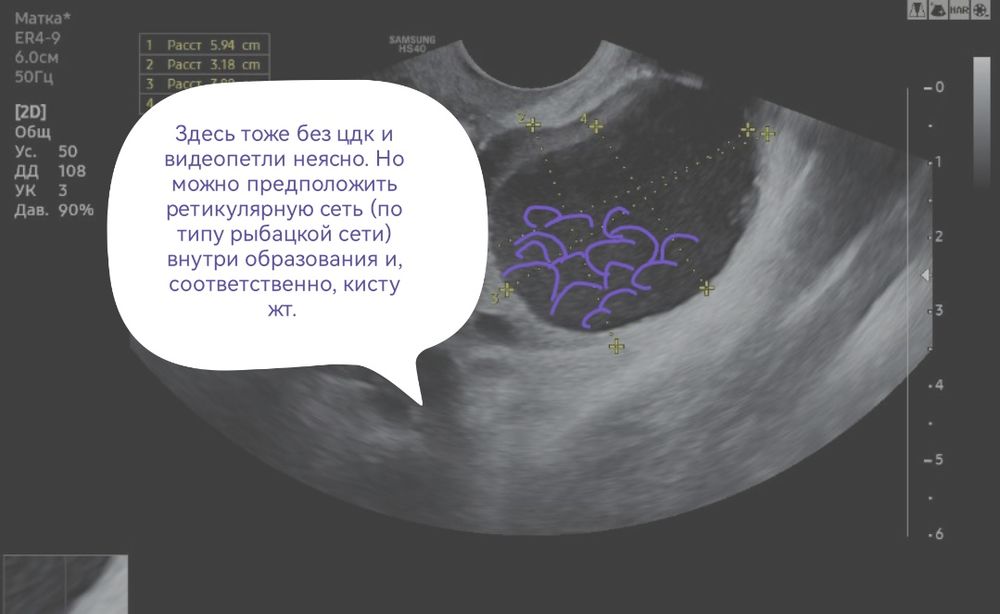

Узи и киста

Сказали киста желтого тела, но я не сильно доверяю, до этого она говорила что обычная киста от фоллика